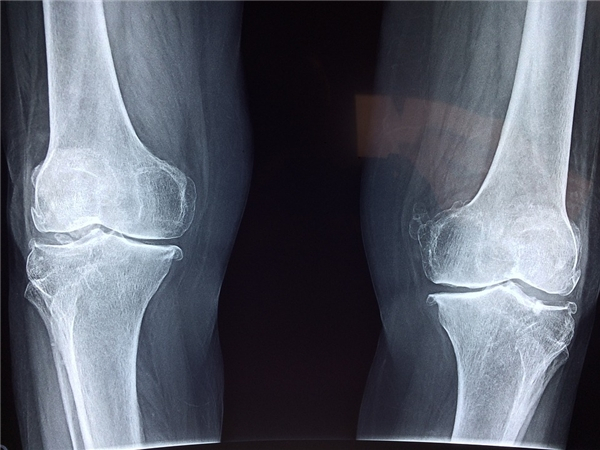

膝关节是人体最大、最复杂的关节。人们常说“人老腿先老”,我们的双腿承载着人体最重的负荷,双腿衰老最突出的是膝关节的病变和衰老。据流行病学统计也表明,有80%的骨性关节病发生在55—65岁的老年人。但是近年来,这种老年病却呈现出年轻化的趋势。

作为一种常见的慢性疾病,膝关节病一般是由于年龄增大,肥胖,劳损,创伤,关节先天性发育异常,以及关节畸形等诸多因素引起的。而中医则对膝关节病有更为独到和透彻的解读,认为由风,寒,湿之邪侵袭机体,痹阻膝关节周围的经络,气血运行不畅是其主要致病的内因。因此驱寒除湿,补充阳气,通经活络非常有助于改善症状。